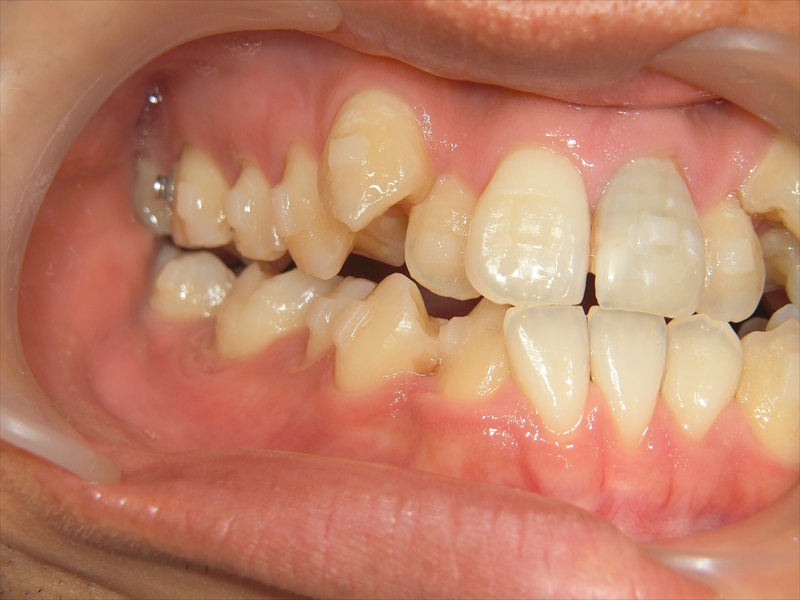

上の歯は歯が並ぶスペースが足りず、八重歯を含むガタガタした歯並びになっていました。

下の歯は、受け口気味で、さらに右下の前から2番目の歯が1本足りない状態でした。

また、歯並び全体がお顔の中心よりも右にずれており、噛み合わせも左右で違っていました。

右側では下の歯が前に出すぎており、左側では逆に下の歯が少し後ろに下がっているという、左右でバランスの取れていない噛み合わせでした。